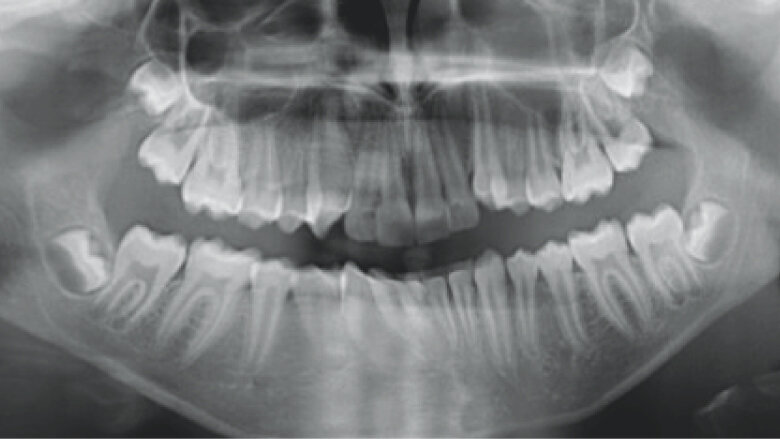

Initial Records

The patient is an 11 year 6 month old male with a chief concern of “overbite.” Diagnostic summary:

Class II, division 1 malocclusion (severe on the right, moderate on the left)

Deep overbite (moderate)

Moderate upper crowding

Mild lower crowding

The slightly retroclined upper incisors and flared lower incisors are consistent with dental compensations for a sagittal jaw discrepancy. The skeletal vertical dimension being within normal limits suggests that the deep bite is predominantly dental in nature.